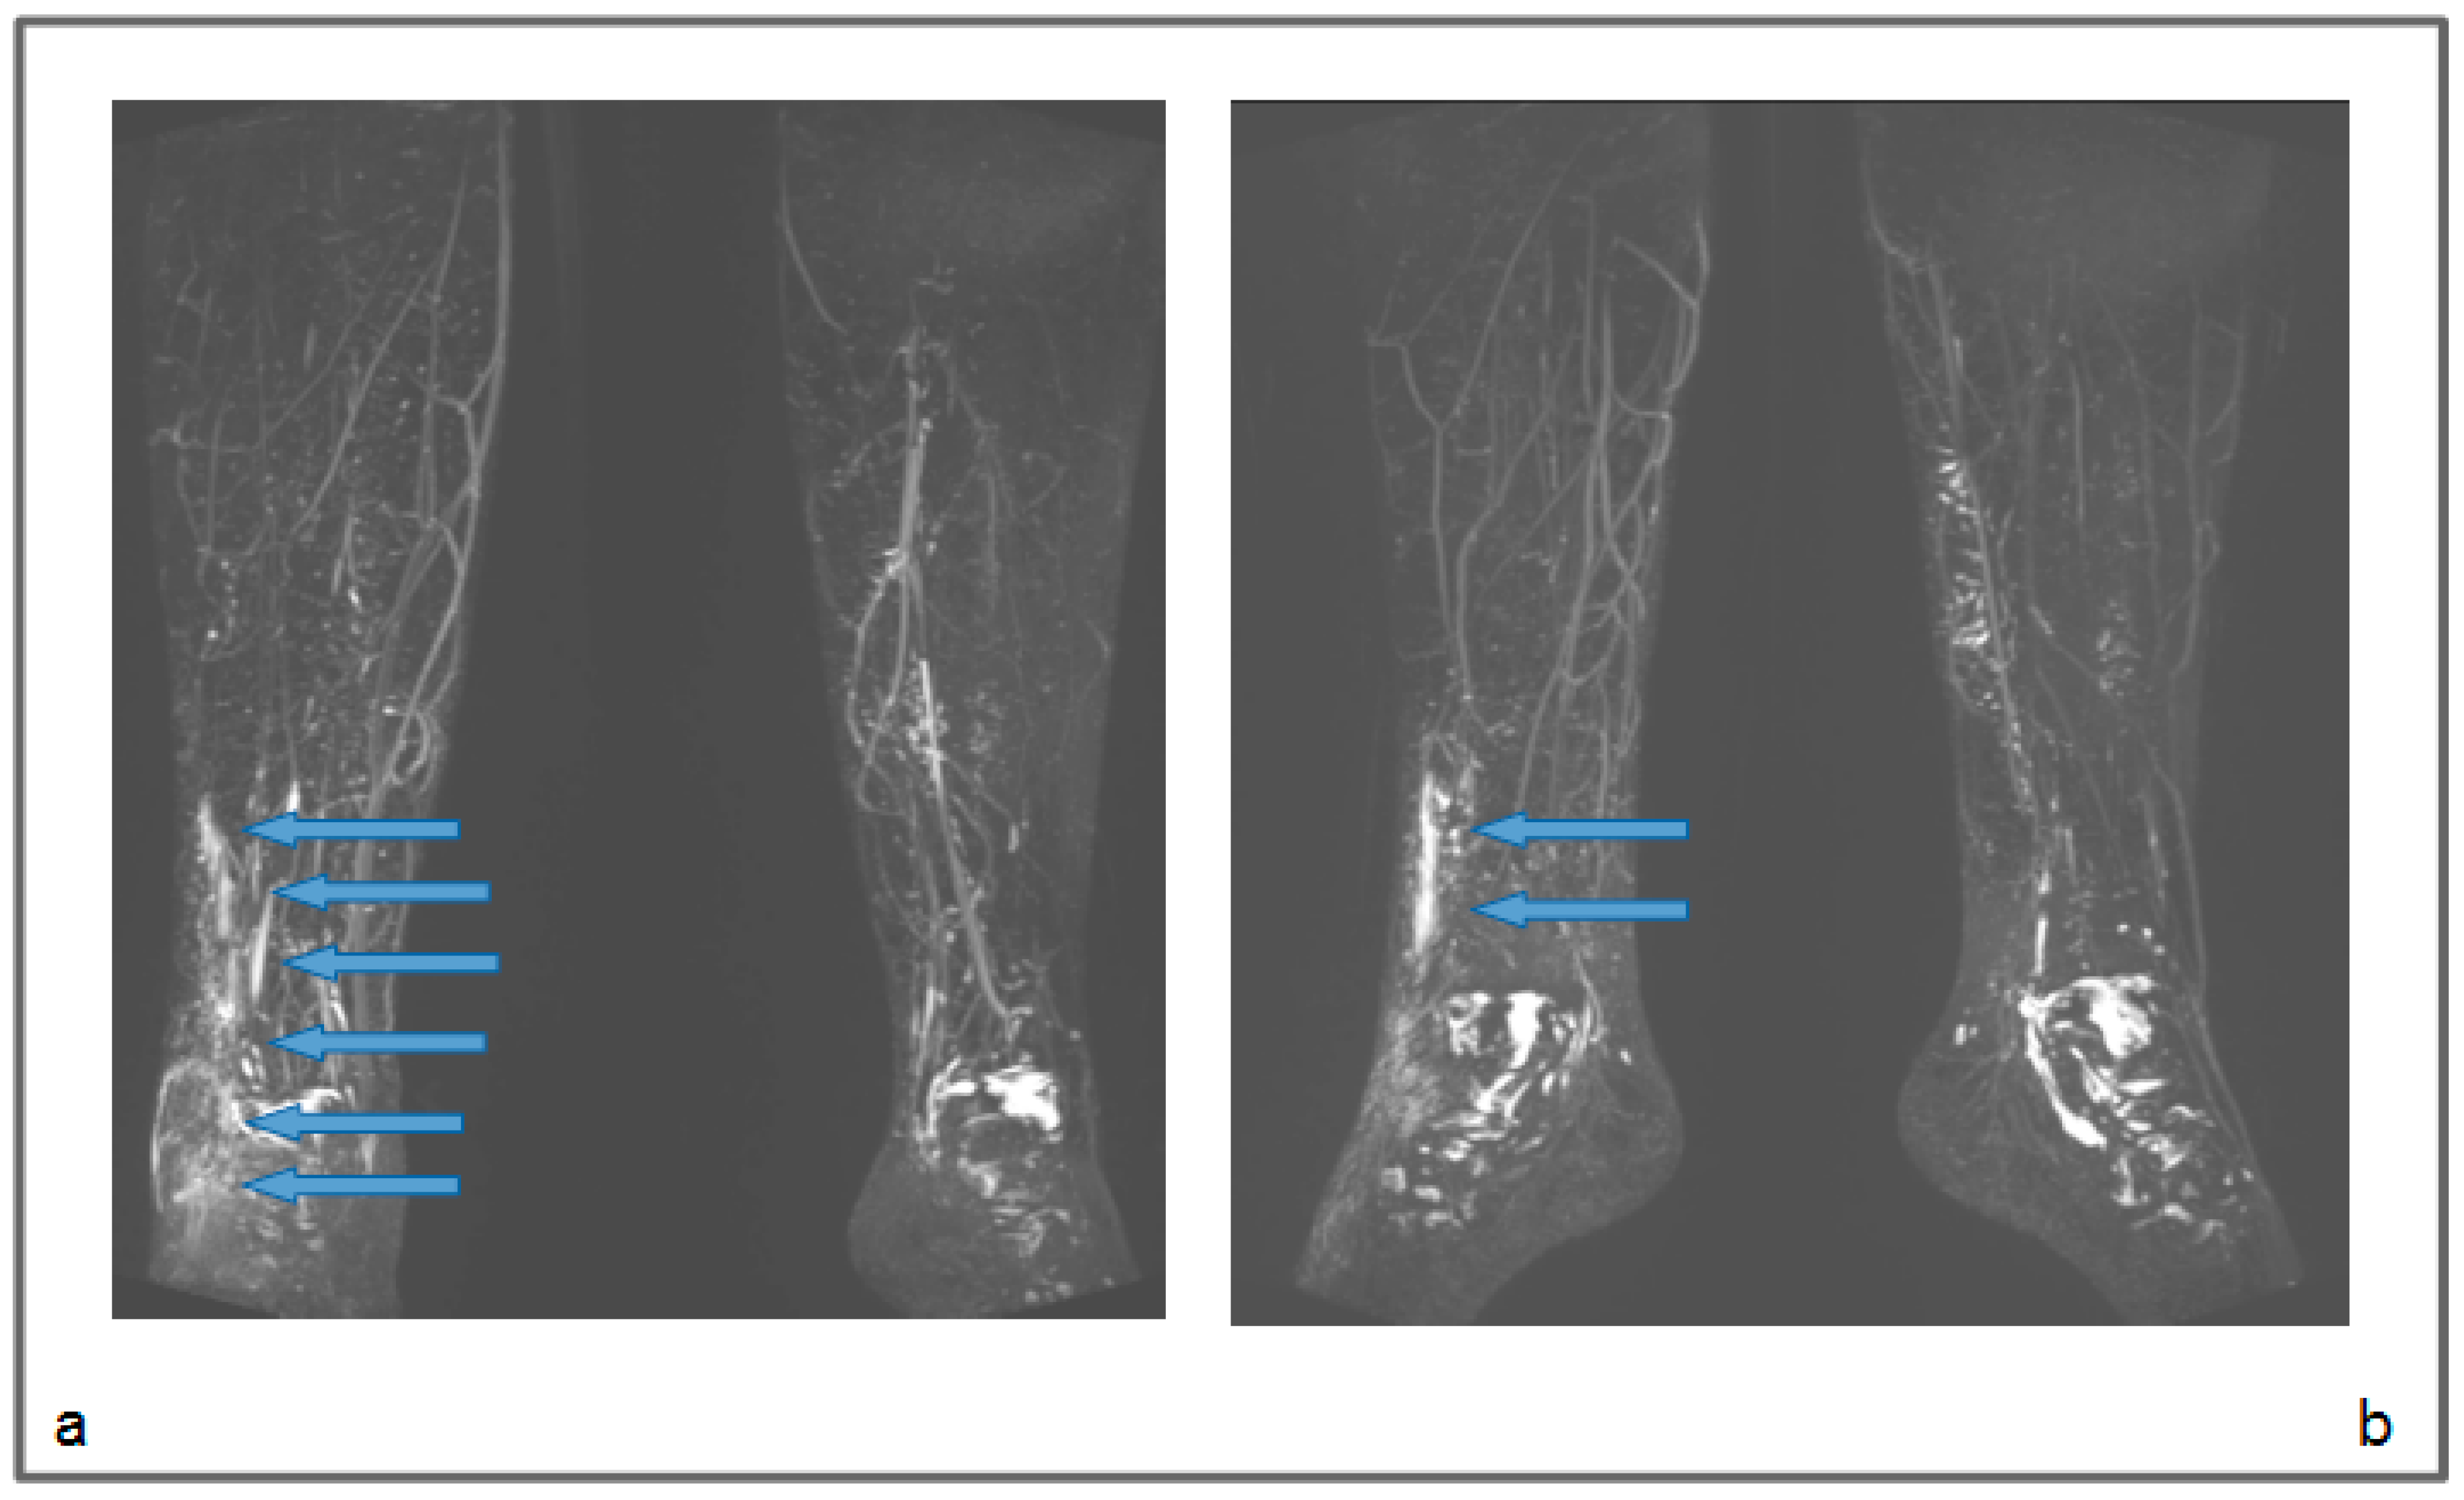

Figure 4.

Patient 1: Preoperative non-contrast MR lymphography (a) and at 1-year follow-up (b). MRI was based on 3D high-spatial-resolution, heavily T2-weighted acquisitions, resulting in a signal loss in the tissue background (like the sequences applied in cholangiopancreatography and MR urography), and enhancement of static fluids like epifascial fluid collections and lymphatic vessels. The follow-up demonstrates the appearance of new inguinal lymphatic vessels (b; blue arrows), that were not visible in the preoperative MR lymphography.